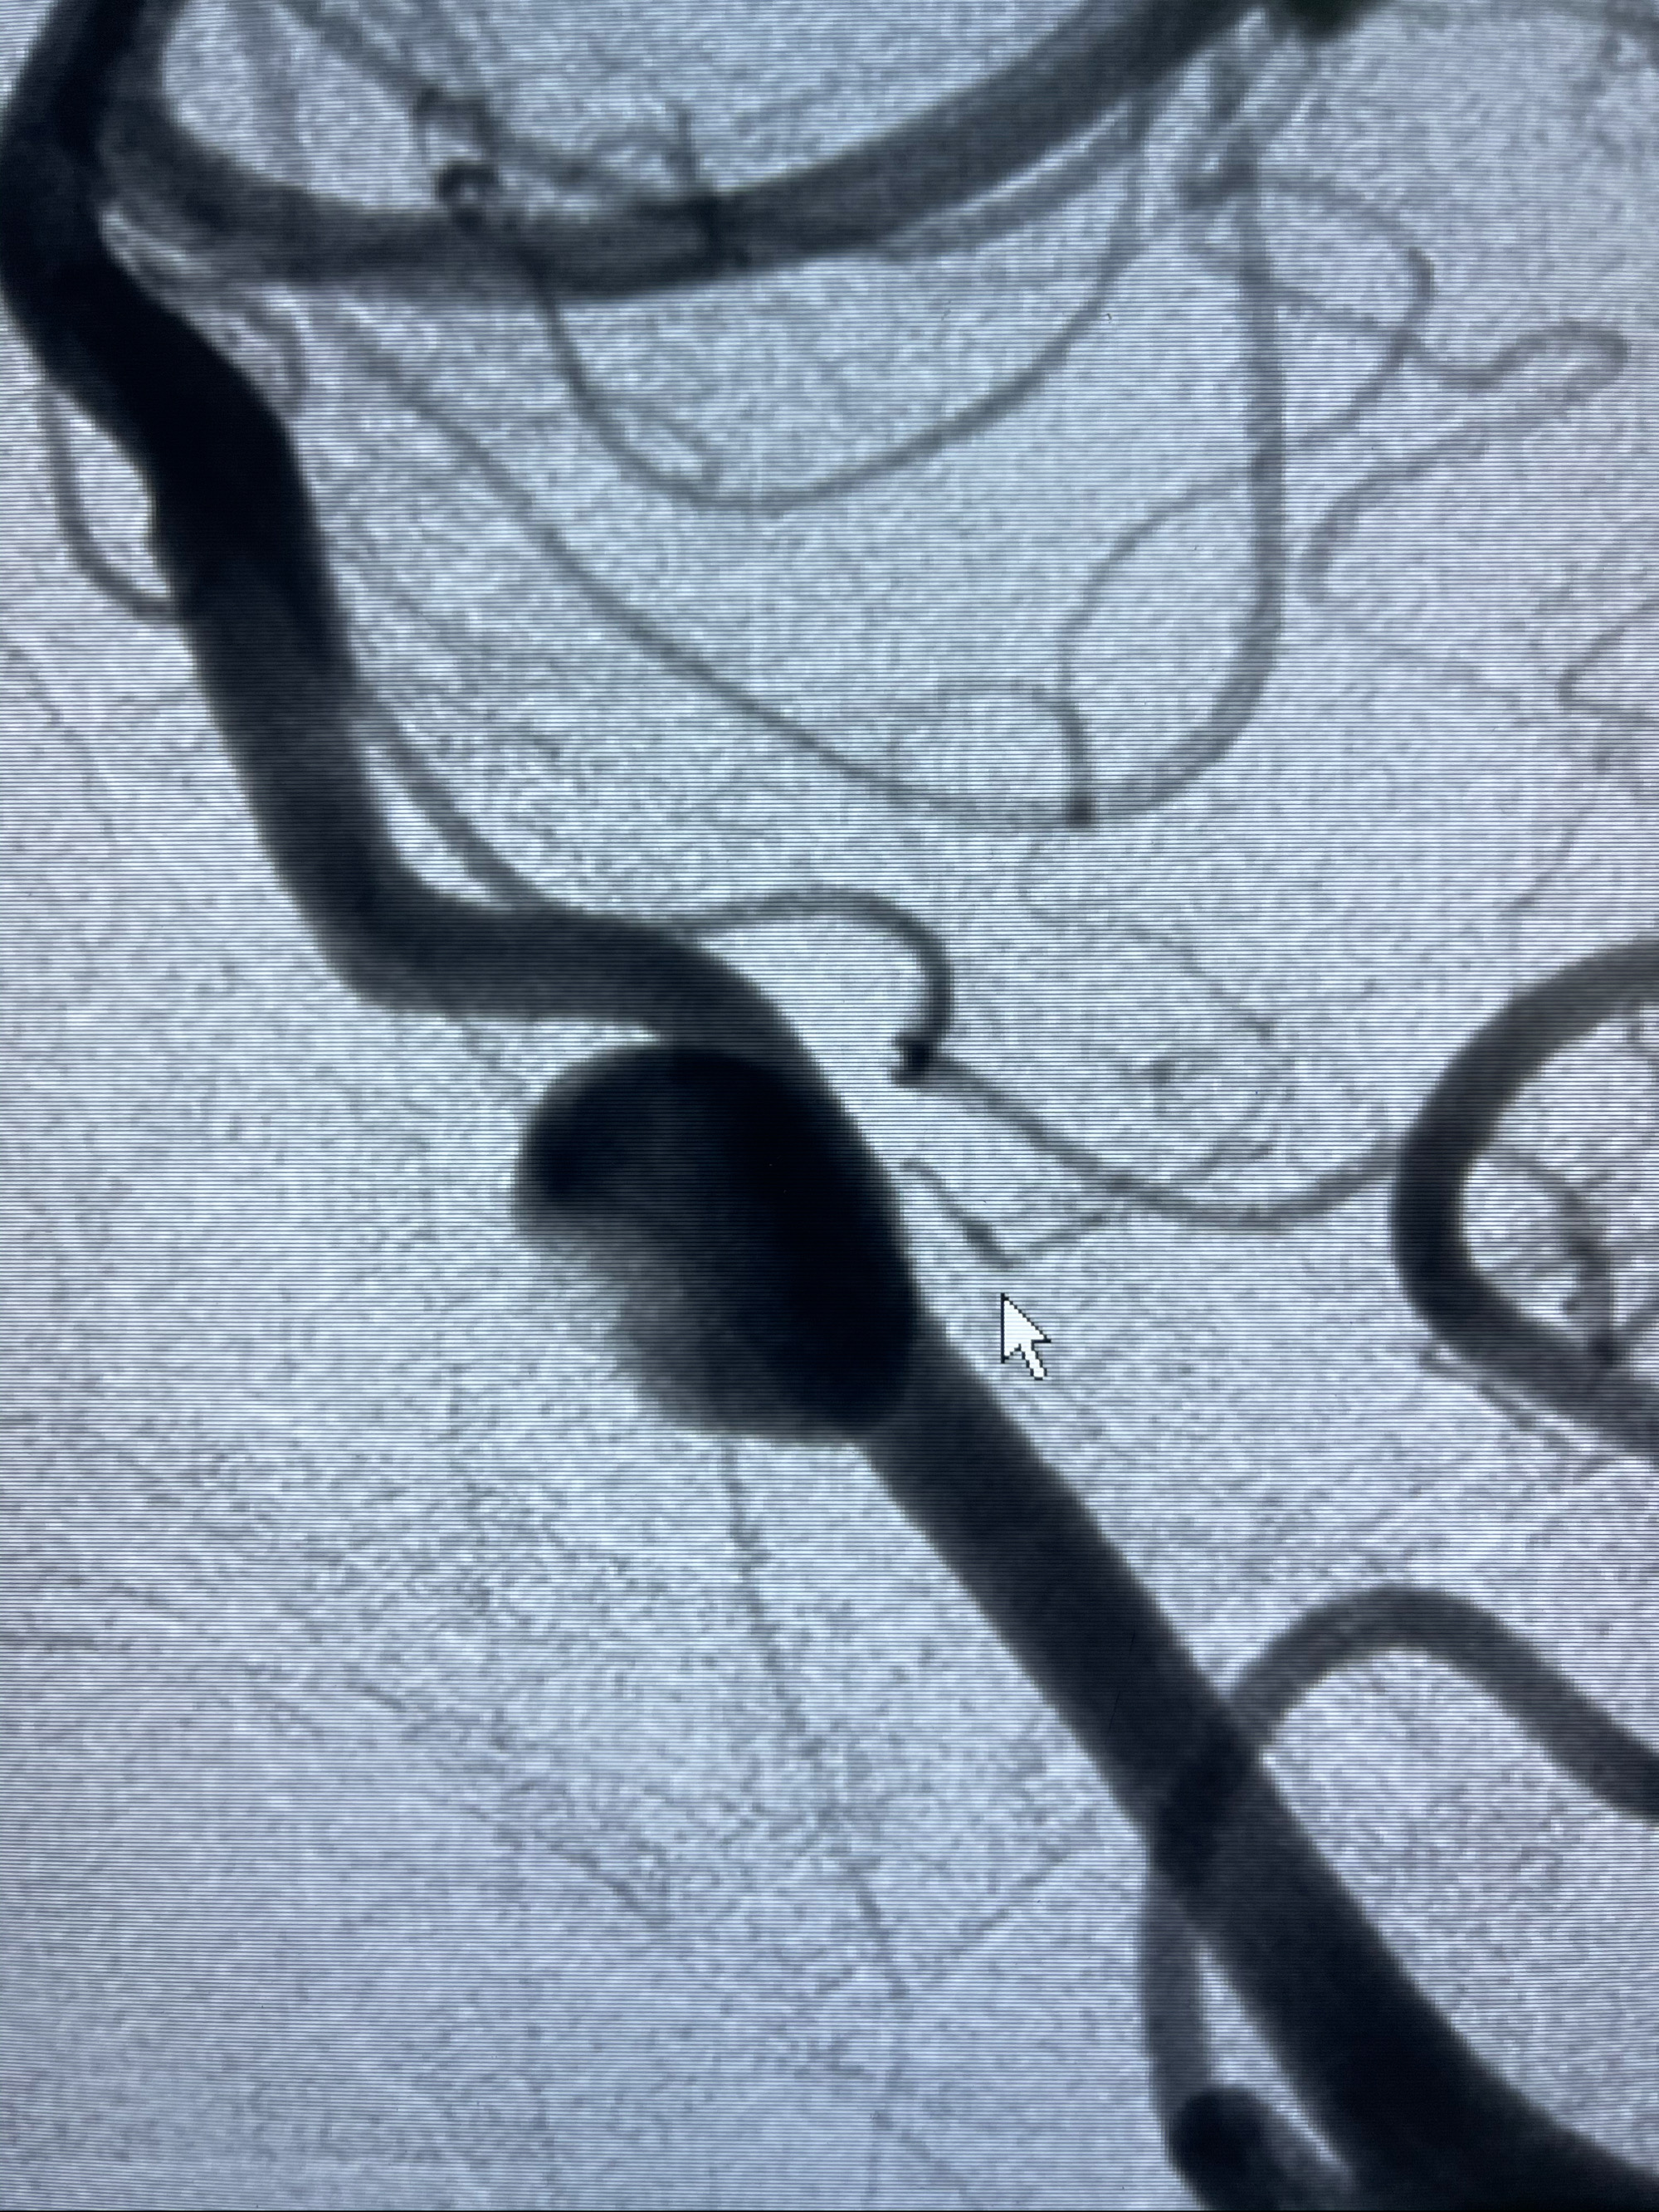

2021-03-08行全脑血管造影

左侧椎动脉V4夹层动脉瘤多支架辅助栓塞:

工作角度造影

即刻造影